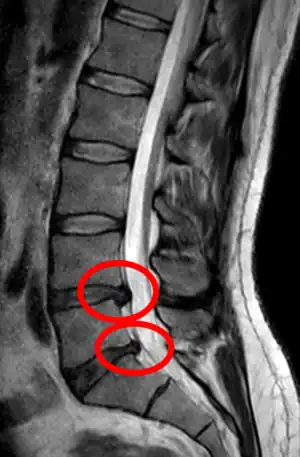

- Magnetic resonance imaging is the gold standard study for confirming a suspected LDH. With a diagnostic accuracy of 97%, it is the most sensitive study to visualize a herniated disc due to its significant ability in soft tissue visualization. MRI also has higher inter-observer reliability than other imaging modalities. It suggests disc herniation when it shows an increased T2-weighted signal at the posterior 10% of the disc. Degenerative disc diseases have shown a correlation with Modic type 1 changes. When evaluating for postoperative lumbar radiculopathies, the recommendation is that the MRI is performed with contrast unless otherwise contraindicated. MRI is more effective than CT in distinguishing inflammatory, malignant, or inflammatory etiologies of LDH. It is indicated relatively early in the course of evaluation (<8 weeks) when the patient presents with relative indications like significant pain, neurological motor deficits, and cauda equina syndrome. Diffusion tensor imaging is a type of MRI sequence used for detecting microstructural changes in the nerve root. It may be beneficial in understanding the changes that occur after herniated lumbar disc compresses a nerve root, and might help in differentiating the patients that need surgical intervention. In patients with a high suspicion of radiculopathy due to lumbar disc herniation, yet the MRI is equivocal or negative, nerve conduction studies are indicated.[44] T2-weighted images allow for clear visualization of protruded disc material in the spinal canal.

A rather severe herniation of the L4–L5 disc

Example of a herniated disc at L5–S1 in the lumbar spine